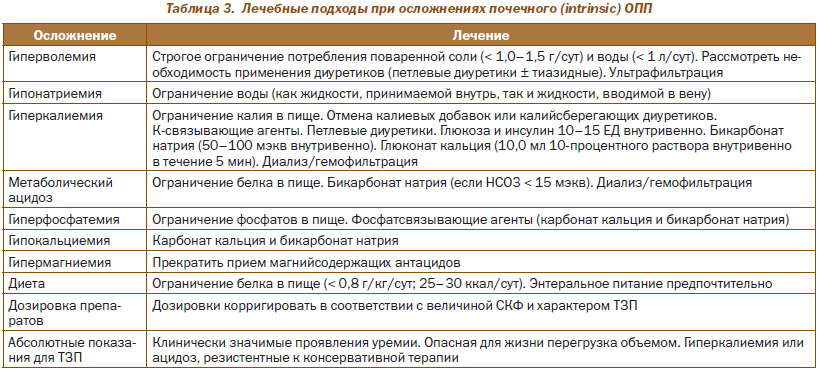

Поддерживающая терапия при почечной (intrinsic) ОПП. Важное место в ведении больных занимают лечебные подходы, направленные на уменьшение или устранение многочисленных метаболических осложнений (гиперволемия, гиперкалиемия, гипермагниемия, гиперфосфатемия, метаболический ацидоз и др.), что показано в табл. 3.